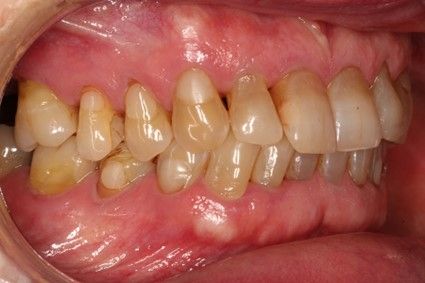

Introducción. El abordaje transcrestal del seno maxilar con y sin material de relleno como injerto es una técnica ampliamente extendida en nuestros días. Generalmente se combina con la utilización de implantes cortos y extracortos. En este trabajo, presentamos una serie de casos tratados con un protocolo unificado con un seguimiento de 10 años.

Material y método. Se ha llevado a cabo un estudio retrospectivo de pacientes tratados mediante implantes extracortos (5,5 y 6,5 mm de longitud) colocados mediante elevación transcrestal sin el uso de injerto. Como variables principales se han estudiado: la pérdida ósea crestal de los implantes y la ganancia en altura sobre el ápice. Como variable secundaria se ha estudiado la supervivencia de los implantes.

Introduction. The transcrestal approach to the maxillary sinus with and without filler material as graft is a widespread technique nowadays. It is usually combined with the use of short and extra-short implants. In this paper, we present a series of cases treated with a unified protocol with a 10-year follow-up.

Material and methods. A retrospective study of patients treated with extra-short implants (5.5 and 6.5 mm in length) placed by transcrestal elevation without the use of a graft was carried out. The main variables studied were: the crestal bone loss of the implants and the gain in height above the apex. Implant survival was studied as a secondary variable.